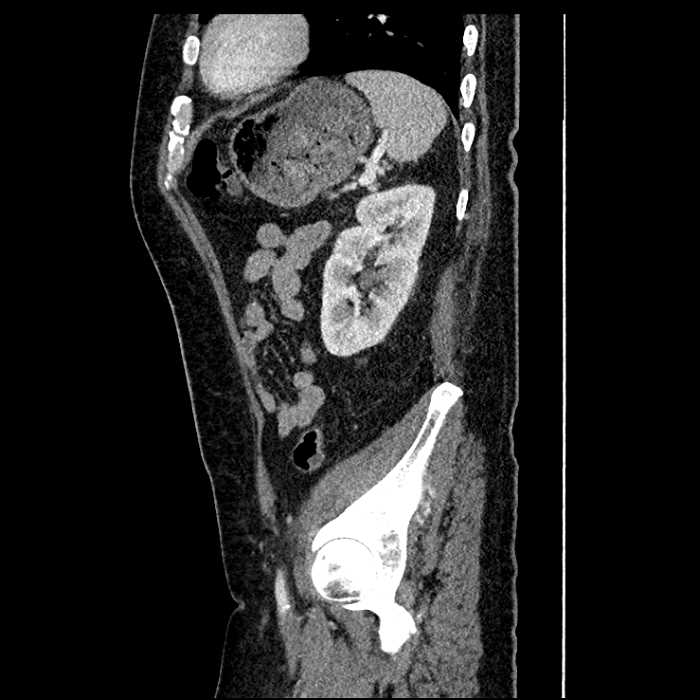

• Large fluid density structure in hepatic segments 7 and 8 measuring 10 x 7 x 7 cm with internal septation and circumferential ill-defined low density compatible with edema

• Peripherally enhancing subcapsular collections along the anterior margin of the left hepatic lobe measuring 3 x 1 cm and 2 x 1 cm

• Clearly marginated fluid density structure in segment 7 and several other scattered tiny hypodensities, which likely represent cysts

• Mild mural thickening of a segment of the sigmoid colon with adjacent fat stranding and a 1.5 cm fluid and gas collection along the tip of an inflamed diverticulum

• Loss of the normal fat plane between this collection and adjacent loops of small bowel, which demonstrate mural thickening

Acute sigmoid diverticulitis complicated by a small contained perforation and a large abscess in the right hepatic lobe. Additional small subcapsular abscesses along the anterior margin of the left hepatic lobe.

Additionally, loss of the normal fat plane between the peridiverticular collection and adjacent thickened loops of small bowel raises the potential for an enterocolonic fistula.

• The classic CT imaging appearance is a double target sign with internal low density surrounded by an internal enhancing rim (capsule) and a low density external rim (edema)

Hepatic abscess showing the double target sign with low density internally surrounded by a thin inner enhancing rim (red arrow) and ill-defined outer low density rim (yellow arrow). Blue arrow indicates an internal septation. Red arrows: additional smaller subcapsular abscesses. Red arrow: focal contained perforation associated with diverticulitis.